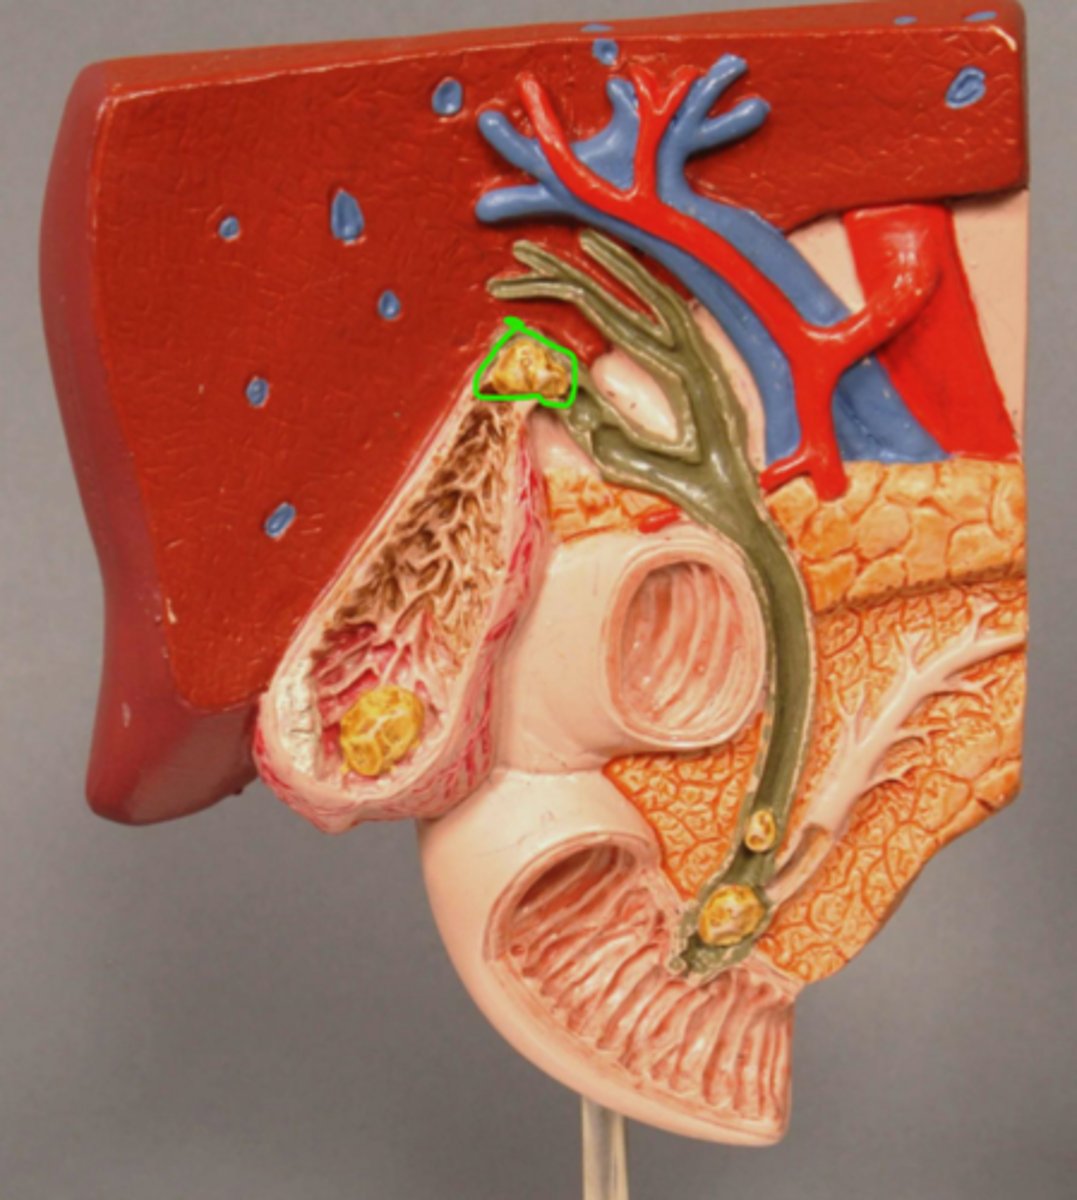

Gallstone at entrance to cystic duct